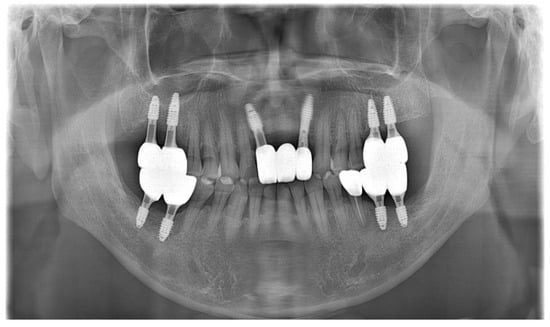

As part of the patient’s ongoing maintenance therapy, follow-up examinations were conducted every six months with routine dental plaque control. When required, additional periodontal treatment was provided during subsequent visits. Annual panoramic radiographs were taken to monitor the long-term prognosis of the implant. At the two-year follow-up, the implant prosthesis remained well maintained and functionally stable within the oral cavity (Figure 11).

Figure 11.

Panoramic radiograph after 2 years.

As ongoing maintenance, six-monthly follow-ups with dental plaque control were conducted. Additional periodontal treatment was provided as required. Annual panoramic radiographs were obtained to monitor implant prognosis. At the two-year follow-up, the implant prosthesis remained stable (Figure 15).

Figure 15.